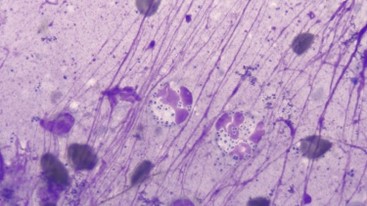

If otitis becomes something you have an interest in, a microscope can be set up in the consult room with a camera and TV attachment, so the owner can see the microbes on the screen (Figure 2). On repeat visits they can then see the microbe number (hopefully!) reduce, making it worth all the effort. This can really motivate them to get involved in their pet’s recovery.